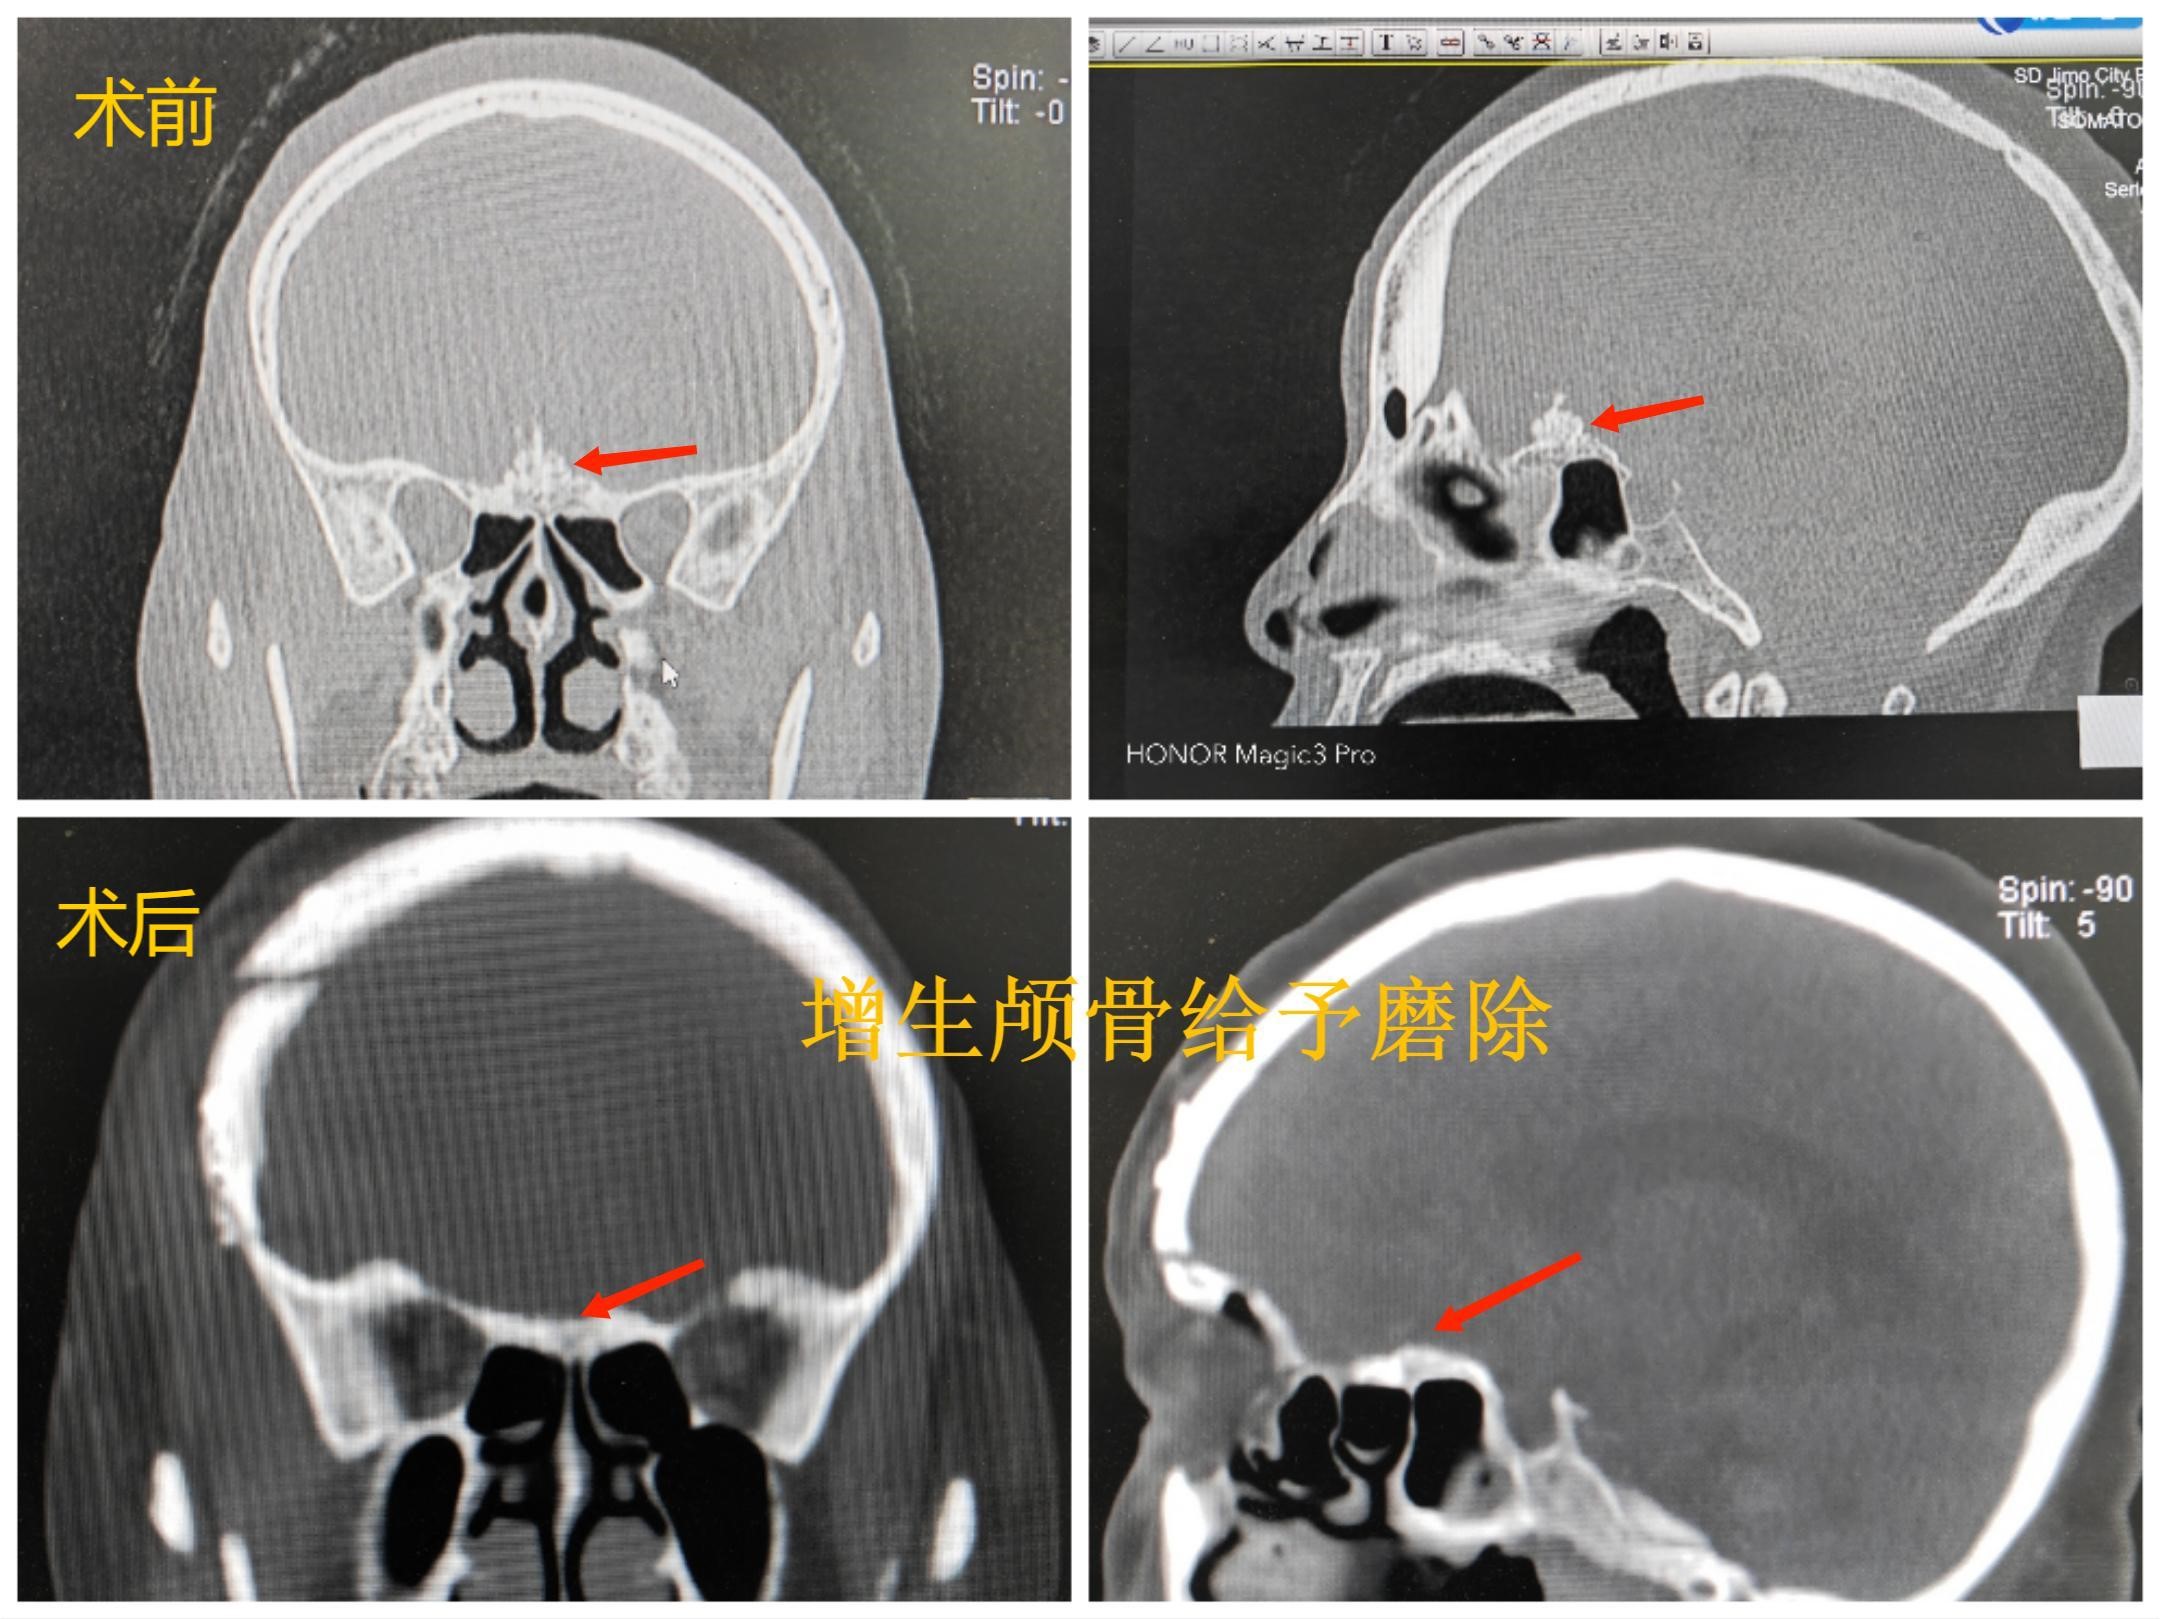

颅脑CT:前颅底占位性病变,颅底骨质增生,瘤内钙化,周围脑组织水肿。

颅骨冠矢状位重建示前颅底骨质明显增生,额窦发达。

手术前后比较:前颅底增生骨质处理情况

注:术后CT骨窗及三维重建